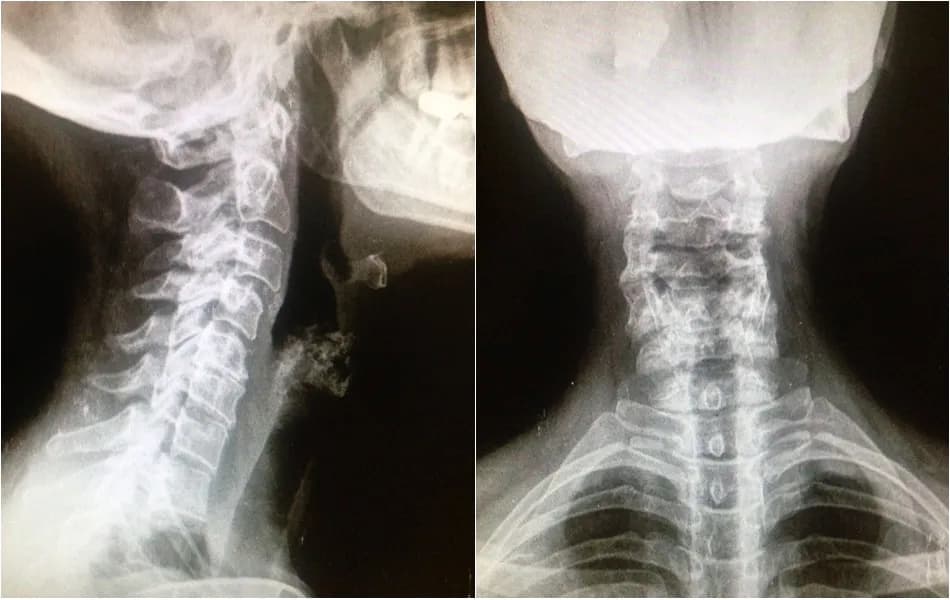

La artrosis cervical grave es una condición que afecta a muchas personas, causando un dolor intenso y persistente en el cuello. Este dolor no solo se limita a la zona cervical, sino que puede extenderse hacia los hombros, brazos, manos y dedos, provocando una serie de síntomas que impactan la calidad de vida. Además del dolor, quienes sufren de esta enfermedad pueden experimentar entumecimiento, hormigueo y debilidad muscular, lo que dificulta tareas cotidianas y puede llevar a una pérdida de fuerza significativa.

La rigidez del cuello es otro síntoma común, que no mejora con el reposo y limita la movilidad. En casos más avanzados, pueden aparecer problemas de coordinación, equilibrio y mareos, lo que sugiere una posible compresión de la médula espinal. Reconocer estos síntomas a tiempo es crucial para evitar complicaciones graves y buscar la atención médica adecuada.

La artrosis cervical grave se manifiesta a través de varios síntomas que afectan de manera significativa la calidad de vida de quienes la padecen. El dolor intenso y persistente en el cuello es uno de los síntomas más comunes, y puede extenderse hacia los hombros, brazos, manos y dedos. Este dolor no solo es incómodo, sino que también puede interferir con las actividades diarias, dificultando tareas simples como conducir o trabajar.

Además del dolor, otro síntoma característico es la rigidez cervical, que no mejora con el reposo y limita la movilidad. Esta rigidez puede generar problemas adicionales, como la dificultad para girar la cabeza o mantener una postura adecuada. La combinación de estos síntomas puede llevar a una disminución en la capacidad para realizar actividades cotidianas, lo que afecta la vida social y laboral de las personas afectadas.